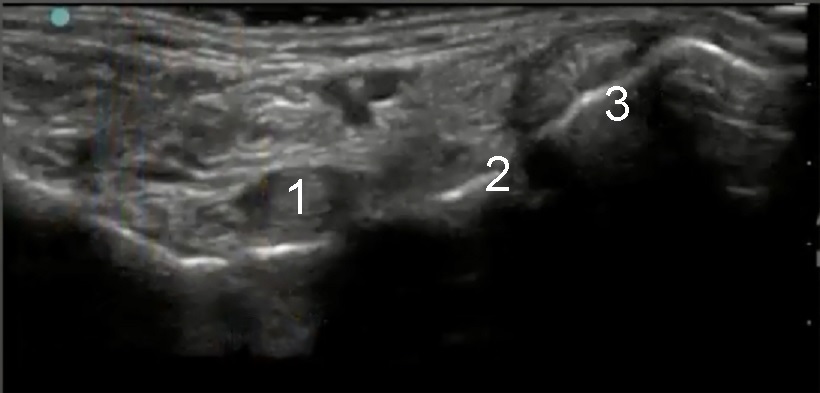

Image 2 - Pied et cheville, Long fléchisseur de l'hallux, état normal

1. Long fléchisseur de l'hallux

2. Long fléchisseur du doigt

3. Tendon du muscle tibial postérieur